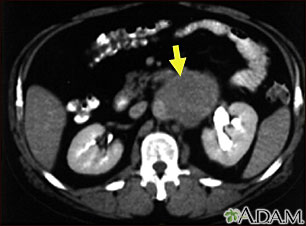

Metastasis is the movement or spreading of cancer cells from one organ or tissue to another. Cancer cells usually spread through the blood or the lymph system.

If a cancer spreads, it is said to have "metastasized."